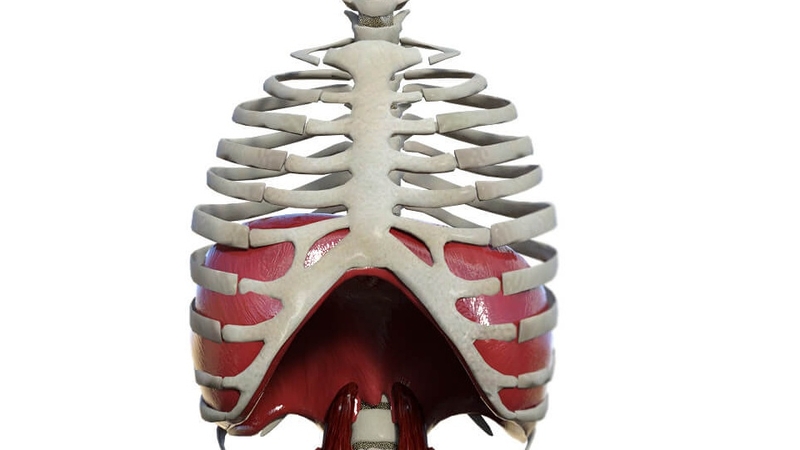

Cơ hoành là một lớp cơ và mô mỏng ngăn cách khoang ngực và khoang bụng. Đó là cơ chính tham gia vào quá trình hô hấp của cơ thể.

Thoát vị hoành bẩm sinh là một khiếm khuyết của cơ hoành. Sự phát triển không hoàn toàn của cơ hoành trước khi sinh khiến cho các cơ quan trong ổ bụng của thai nhi có thể bị đẩy vào khoang ngực và cản trở sự phát triển hình thành phổi.